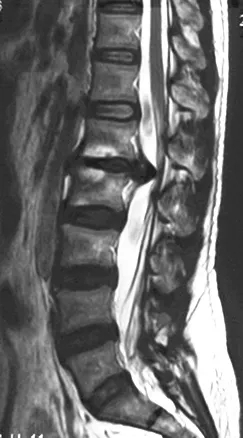

? 術(shù)前磁共振

據(jù)悉,來(lái)自安康市的女性患者因?yàn)殚L(zhǎng)期久坐辦公出現(xiàn)腰椎間盤(pán)突出癥,在當(dāng)?shù)貒L試多種保守治療均無(wú)效,因?yàn)楣ぷ髅σ矝](méi)有進(jìn)行系統(tǒng)化治療。6月中旬工作勞累后,患者病情突然加重,腰部以及雙下肢劇烈疼痛,伴有麻木和無(wú)力感,臥床無(wú)法下地。一天后大小便排便也出現(xiàn)困難。當(dāng)?shù)蒯t(yī)院檢查后診斷為腰椎間盤(pán)巨大突出,壓迫神經(jīng)程度嚴(yán)重,突出部位在脊髓圓錐部位手術(shù)風(fēng)險(xiǎn)大,術(shù)后恢復(fù)較差,建議到空軍軍醫(yī)大學(xué)西京醫(yī)院接受治療。

入院時(shí),患者臥床不能自理,雙下肢劇烈疼痛讓患者連續(xù)幾個(gè)晚上睡覺(jué)都十分困難。查體顯示雙側(cè)髂腰肌肌力II級(jí),雙側(cè)股四頭肌力III級(jí),遠(yuǎn)端肌力輕度減低。鞍區(qū)感覺(jué)減退,肛門(mén)括約肌輕度松弛,小便費(fèi)力。綜合影像學(xué)檢查結(jié)果診斷為腰1/2椎間盤(pán)脫出,馬尾綜合癥。6月25日,在空軍軍醫(yī)大學(xué)西京醫(yī)院脊柱外科王哲主任安排下,丁坦副教授主刀實(shí)施腰1/2椎板切除減壓,髓核摘除,椎間植骨融合內(nèi)固定術(shù),手術(shù)用時(shí)2小時(shí)順利結(jié)束。